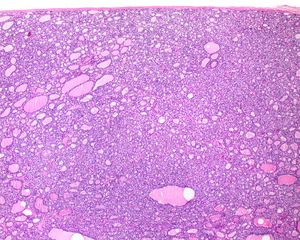

كبسولة ورم الغدة الدرقية NIFTP

لا يوجد دليل على غزو كبسولة النسيج الضام الليفي جيدة التكوين ، مما يساعد على دعم تشخيص NIFTP.

1) مغلفة أو مغلفة جزئيا. عادة ما تكون الأورام محددة جيدًا أو محوطة ، مع تغليف أغلبيتها ، ومحاطة بكبسولة نسيج ضام ليفية جيدة التكوين.

2) الغياب التام للغزو من أي نوع في الورم الذي تم تقييمه بعناية باستخدام الكبسولة الكاملة للأفة الكاملة التي تم أخذ عينات منها.

3) نمط النمو الجريبي في الغالب. لا ينبغي أن تكون الهياكل الحليمية موجودة. علاوة على ذلك ، يجب أن تكون البنية الصلبة أو المعزولة أو التربيقية أقل من 30 ٪ من الورم الكلي حتى تظل هذه الفئة سارية. يمكن التعرف بسهولة على المادة الغروانية (المادة التي تفرزها الخلايا الحويصلية للغدة الدرقية) في جميع الأنحاء.